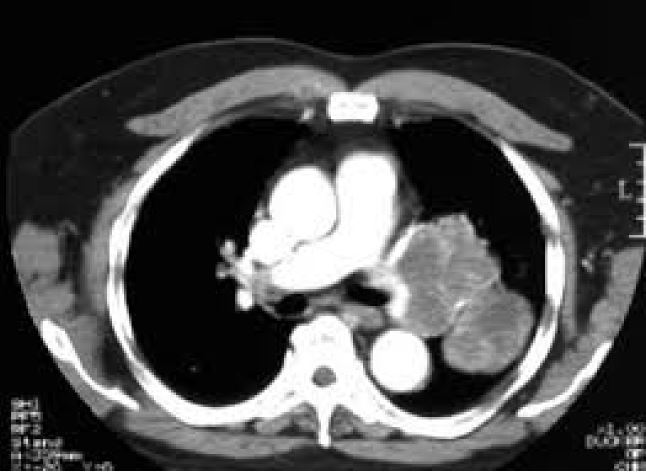

Q

-imaging modality -orientation -window -body part -iv contrast -abnormality

A

-CT -axial -lung -chest -yes -left lung carcinoma